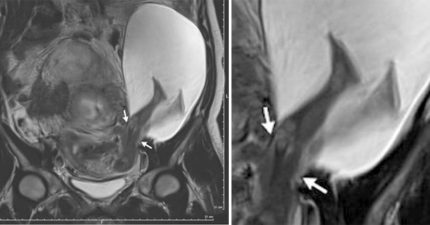

懷孕多次媽媽去照超音波照,拍到恐怖「寶寶一腳穿出子宮」全世界只有26起案例!